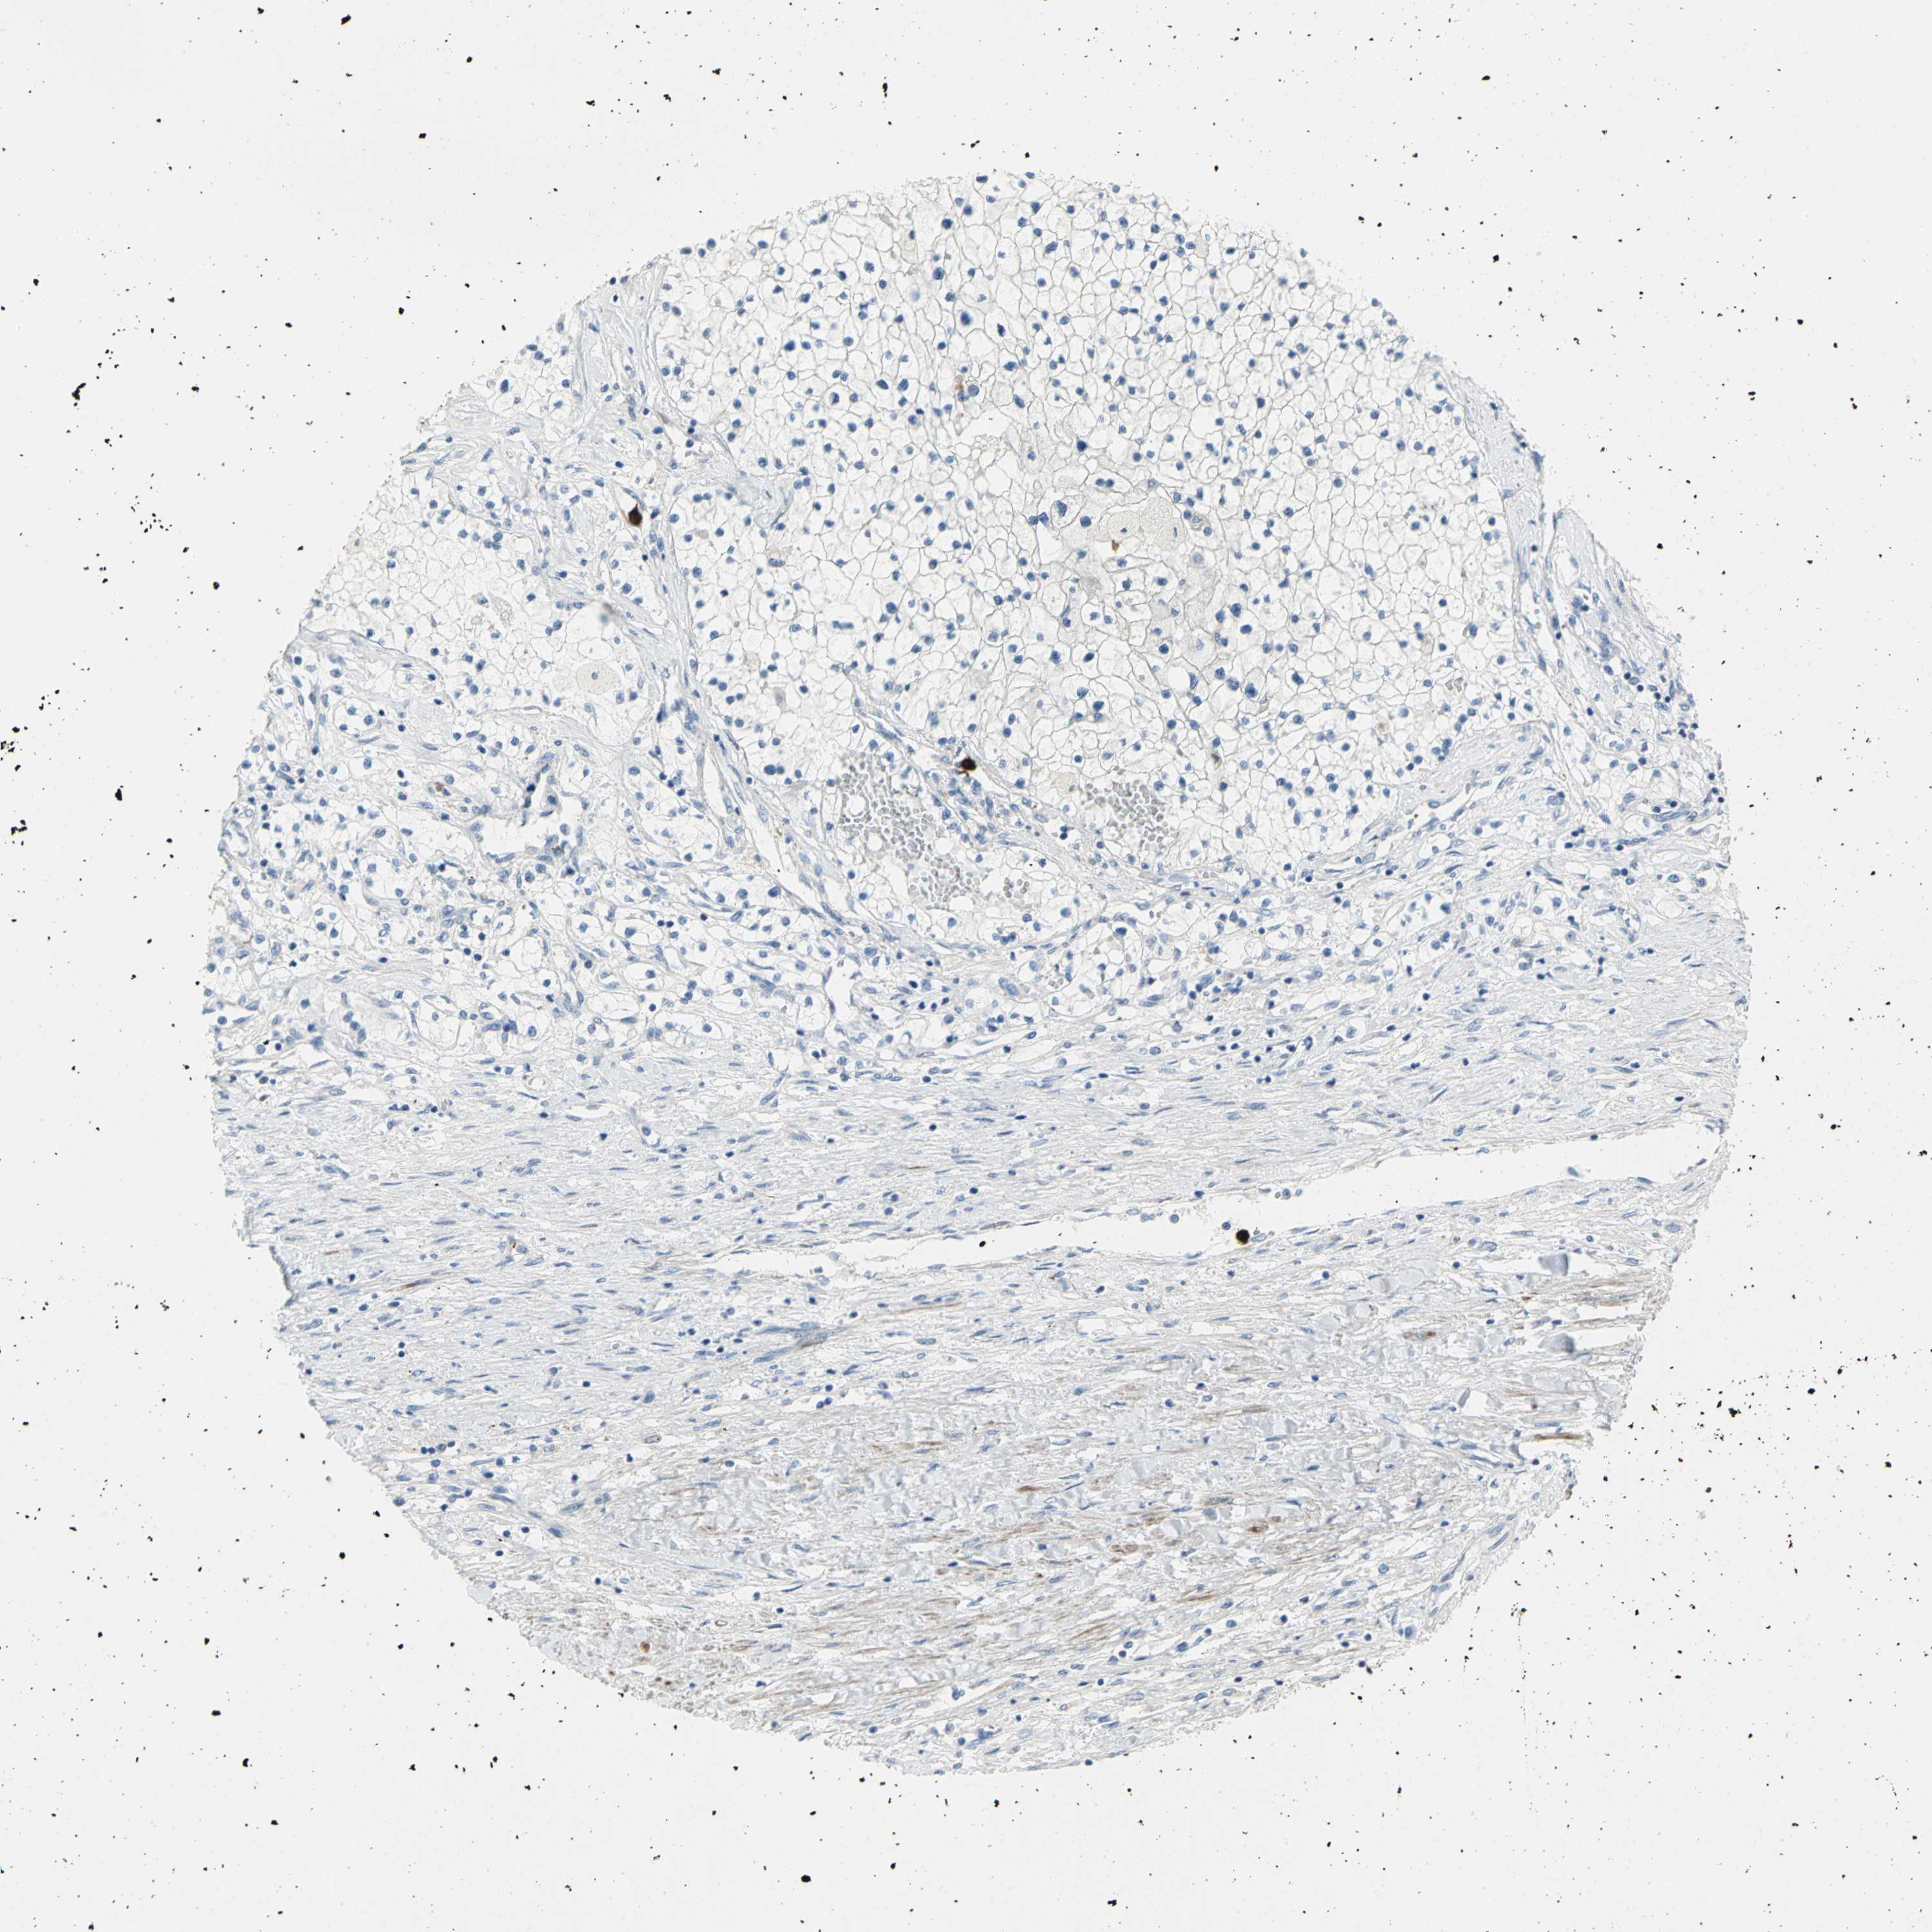

KIDNEY RENAL PAPILLARY CELL CARCINOMA (TCGA) - Interactive survival scatter ploti

The Survival Scatter plot shows the clinical status (i.e. dead or alive) for all individuals in the patient cohort, based on the same data that underlies the corresponding Kaplan-Meier plots. Patients that are alive at last time for follow-up are shown in blue and patients who have died during the study are shown in red.

The x-axis shows the expression levels (FPKM) of the investigated gene in the tumor tissue at the time of diagnosis. The y-axis shows the follow-up time after diagnosis (years). Both axes are complimented with kernel density curves demonstrating the data density over the axes. The top density plot shows the expression levels (FPKM) distribution among dead (red) and alive patients (blue). The right density plot shows the data density of the survived years of dead patients with high and low expression levels respectively, stratified using the cutoff indicated by the vertical dashed line through the Survival Scatter plot. This cutoff is automatically defined based on the FPKM cutoff that minimizes the p-score. The cutoff can be changed by dragging the vertical line or by entering a cutoff value in the square labeled "Current cut-off".

Under the Survival Scatter plot the p-score landscape (black curve; left axis) is shown together with dead median separation (red curve; right axis). Dead median separation is the difference in median mRNA expression between patients who have died with high and low expression, respectively. It is calculated as follows: median FPKM expression of dead patients with high expression - median FPKM expression of dead patients with low expression. This is intended to aid the user in visually exploring custom cutoffs and the associated p-scores and dead median separation.

Individual patient data is displayed and can be filtered by clicking on one or more of the category buttons on the top of the page. Categories describing expression level and patient information include: high, low, alive, dead, female, male and tumor stages. The scale of the x-axis can be toggled between linear and log-scale by clicking on the "x log" button. Mouse-over function shows TCGA ID, patient information and mRNA expression (FPKM) for each patient.

& Survival analysisi

Kaplan-Meier plots summarize results from analysis of correlation between mRNA expression level and patient survival. Patients were divided based on level of expression into one of the two groups "low" (under cut off) or "high" (over cut off). X-axis shows time for survival (years) and y-axis shows the probability of survival, where 1.0 corresponds to 100 percent.

ALOX15 is not prognostic in Kidney Renal Papillary Cell Carcinoma (TCGA)

TCGA RNA samplesi

RNA-seq data is reported as average FPKM (number Fragments Per Kilobase of exon per Million reads), generated by the The Cancer Genome Atlas (TCGA) .

Normal distribution across the dataset is visualized with box plots, shown as median and 25th and 75th percentiles. Points are displayed as outliers if they are above or below 1.5 times the interquartile range. FPKM values of the individual samples are presented next to the box plot.

Average pTPM 0.0

Number of samples 282